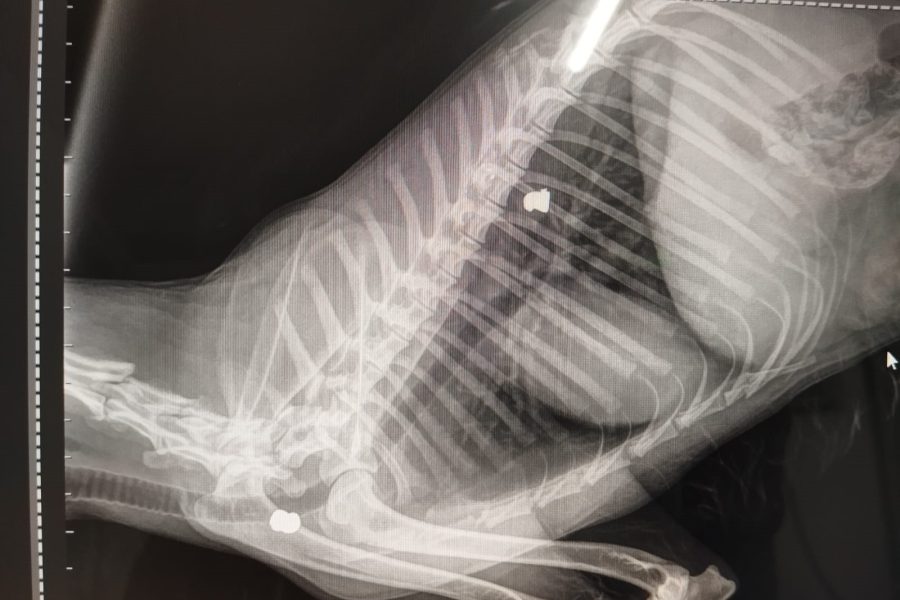

Durante los estudios clínicos, se detectaron indicios de un posible atropellamiento, ya que el animal presentaba parálisis en el tren posterior. No obstante, una serie de radiografías reveló la presencia de balines encapsulados en diferentes zonas del cuerpo, lo que indicaría heridas de vieja data. La veterinaria Andrea Gangone explicó que se hallaron proyectiles en el lomo, la mandíbula y en la zona torácica. “En su piel no había heridas nuevas, pero sí signos de lesiones antiguas. Le administramos medicamentos para el dolor e inflamación y permanece estable, aunque decaída y recibiendo suero”, detalló.